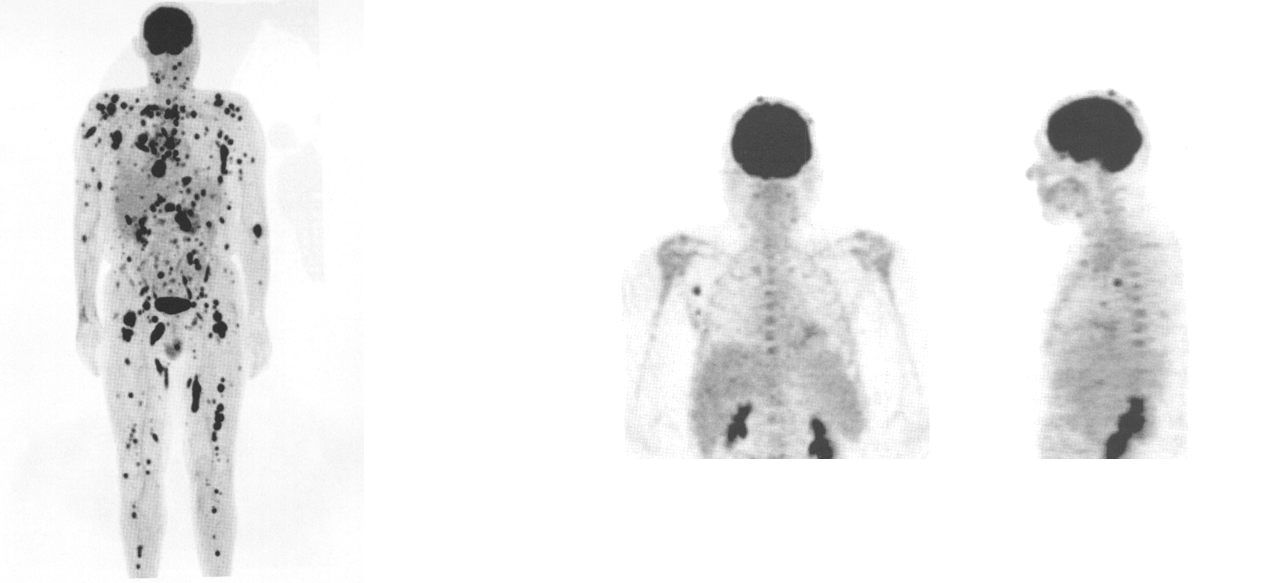

what does this image show

melanoma (diffuse) whole body

melanoma (scale area)

what is the indication for a total body PET scan

malignant melanomas